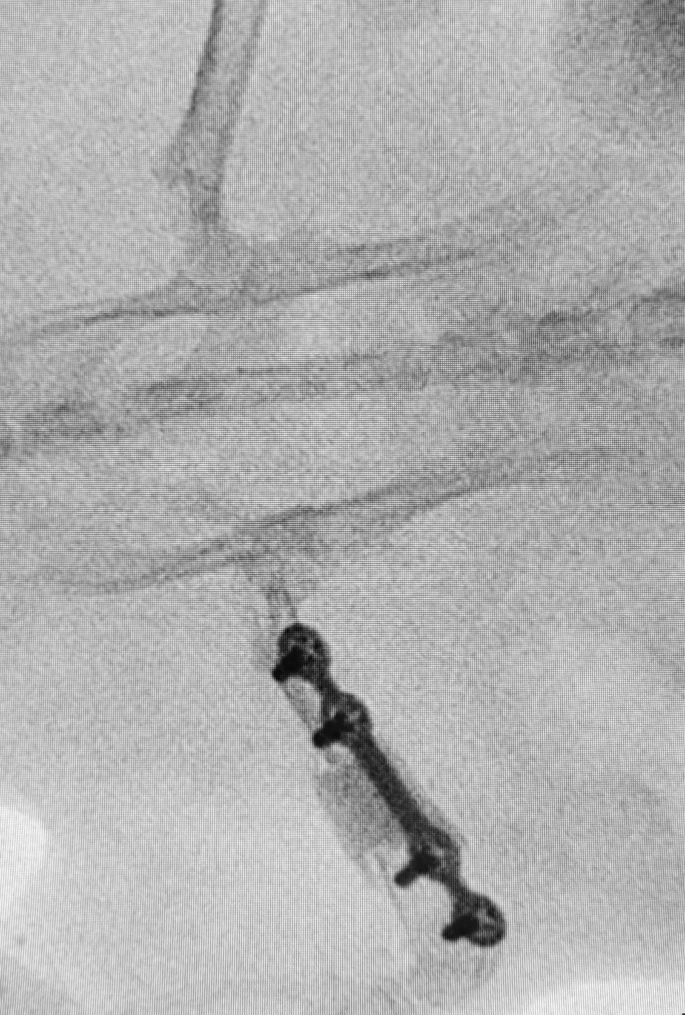

All surgical procedures were performed under aseptic conditions. General anesthesia was induced in a chamber delivering a 4–5% isoflurane/O2 gas mixture, and the anesthetic state was maintained with a 1.5–2.5% isoflurane/O2 gas mixture with an adapted ventilation facemask. Each animal received an intramuscular injection of buprenorphine hydrochloride (0.05 mg/kg) pre-operatively. Rats were placed in the left lateral decubitus position. The right leg of each rat was shaved and scrubbed twice with chlorhexidine solution. The femur was exposed through a lateral approach. A longitudinal incision was made along the femur to expose the fascia lata. Then, the space between the vastus lateralis and the biceps femoris was developed. A plate was placed on the anterolateral aspect of the exposed femur. Two types of osteosynthesis (MODUS®, Medartis™, Switzerland) were performed: group one (10 rats) had 1 mm-thick 4-hole titanium plates (29 mm in length) and 4 cortical screws 2 mm in diameter (6 mm in length), and the group two (9 rats) had 0.6 mm-thick 6-hole titanium plates (30 mm in length) and 4 cortical screws 1.5 mm in diameter (6 mm in length) (2 for proximal and 2 for distal holes) (Fig. 1). After verification of placement, bicortical holes were drilled, and the plate was secured with the screws. Then, a 7 mm femoral defect was made in the diaphysis of the femur underneath the plate using a Gigli saw. PMMA cement (Palacos® R + G, Heraeus Medical™) was mixed according to the manufacturer’s protocol and was molded into the femoral defect, which was slightly wider than the femoral diameter (Fig. 1). After full polymerization of the cement, the wound was irrigated with sterile saline, and the incision was closed in two layers (muscular and subcutaneous) with interrupted 4–0 sutures (Vicryl®, Ethicon™, Johnson & Johnson™, Somerville, NJ). The bioglue (Dermabond®, Ethicon™, Johnson & Johnson™) was subsequently applied to the closed skin incision. Post-operatively, the rats were allowed to return to full weight bearing immediately. Analgesia comprised subcutaneous injection of buprenorphine hydrochloride (0.05 mg/kg) and meloxicam (2 mg/kg) twice a day for 3 to 7 days. After the fourth-week examination, the rats in Group 1 underwent 2nd stage of IMT, as this protocol was part of a broader protocol involving femoral defect models. The rats in Group 2 were euthanized painlessly under general anaesthesia (5% isoflurane/O2 gas mixture) with an intracardiac injection of pentobarbital (500 mg/kg) (DOLETHAL®, Vetoquinol™, Lure, France).

Intraoperative views and surgical steps of a 1 mm thick plate positioning in the induced membrane technique. (A) Circumferential exposition of the femoral shaft with a periosteal elevator protecting the medial structures. (B) Fixation of a 4-hole plate and screws. (C) The femoral defect was created with a Gigli saw and measured (7 mm). (D) Bone cement in place before closure.